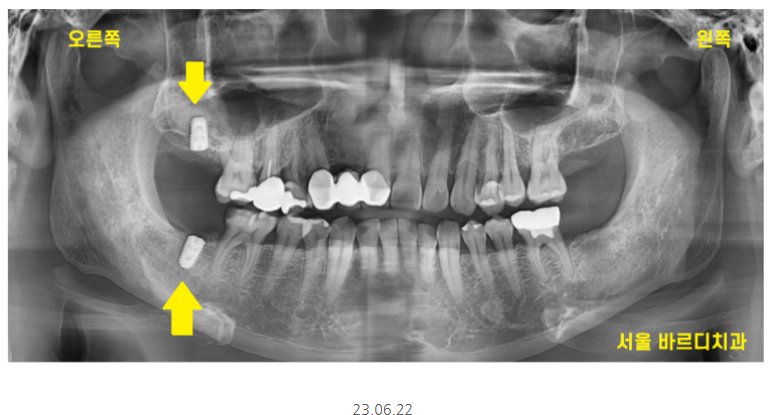

그리고 다음번 임플란트 체크에 오셔서

"왼쪽도 해버리려고요.

임플란트 위아래로 해주세요"

처음에 오른쪽만 원하셨었는데

한쪽 받아보시고

반대편까지 진행하셨어요.